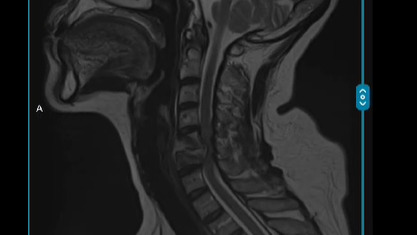

Hace unos cuentos días sufrí una caída la cual me provoco una lesión (fractura) en mi 5ta cervical la cual me ha impedido tener movilidad en mis extremidades y a la mayor espera puede provocarme problemas respiratorios y una cuadraplejia permanente.

A few days ago I suffered a fall which caused an injury (fracture) in my 5th cervical which has prevented me from having mobility in my limbs and to the greater expectation can cause breathing problems and a permanent quadriplegia.